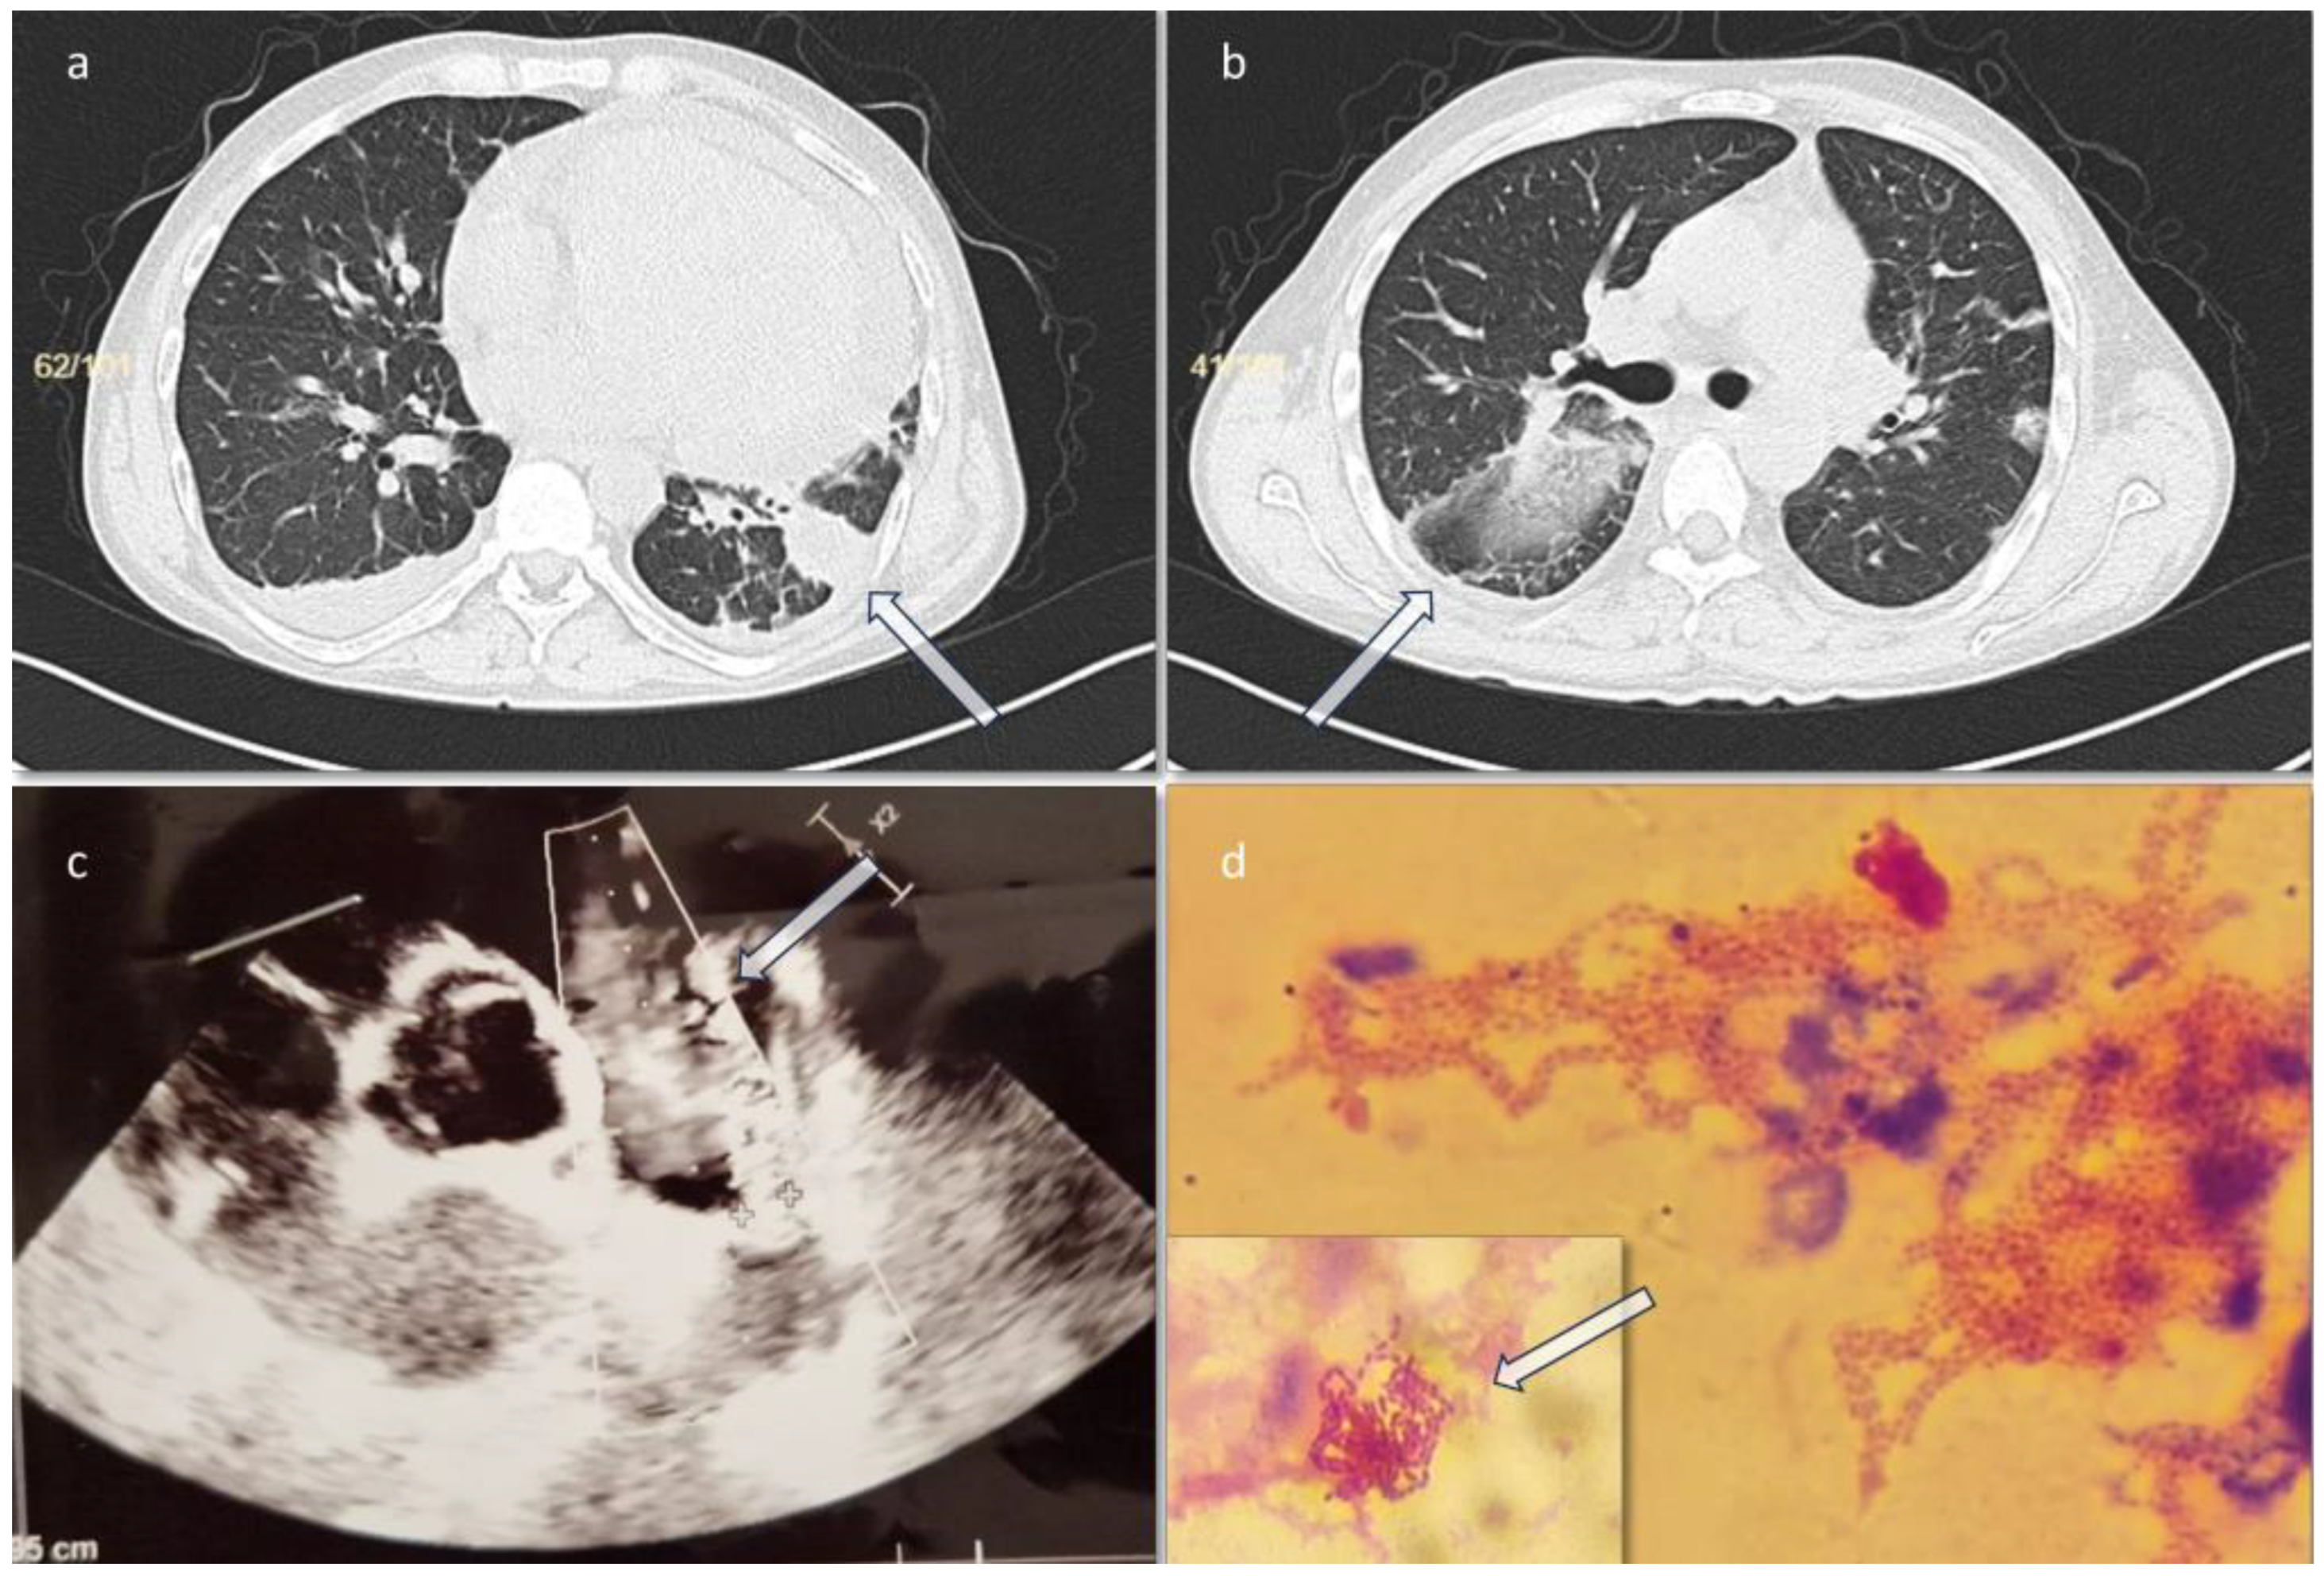

On day 3 he presented an episode of sinus tachycardia. A cardiology consult and a transthoracic sonography were performed, showing a filamentous formation of 1 cm attached to the pulmonary valve, suggestive for valve vegetations, and a persistent ductus arteriosus (PDA) (Figure 1). The left ventricular ejection fraction (LVEF) was 45%. Treatment with metoprolol (50 mg every 24 hours) was initiated and a suspicion of infective endocarditis was raised. In this context, the antibiotic treatment started with piperacillin-tazobactam was continued, and vancomycin (1 g every 12 hours) was added to cover the possibility of Gram-positive cocci involvement.

Chest CT scan performed on the third day of admission revealed two filling defects of approximately 12 mm and 10 mm respectively, at the level of the pulmonary artery trunk – possibly thrombotic images/vegetation/mediastinal adenopathies, for which deep vein thrombosis prophylaxis with enoxaparin (0.6 mL every 12h for 14 days then 0.6 mL every 24h for another 7 days) was initiated (as the cardiologist recommended), an inhomogeneous image of approximately 6/3.5 cm at the level of the left lung lower lobe, posterior and lateral segments, with mixed densities (liquid and air) suggestive of a partially evacuated lung abscess (Figure 1a, 1b). On day 4 the result for blood cultures was positive with A. actinomycetemcomitans. Subsequently, the antibiotic treatment was deescalated to ceftriaxone (2 g/day), to which both A. actinomycetemcomitans and K. pneumoniae were susceptible.

Figure 1. a,b. Chest computed tomography: infiltration in the both lungs. c. Transthoracic echocardiography, showing PDA. d. Gram staining from the hemoculture bottle, showing Gram-negative rods.